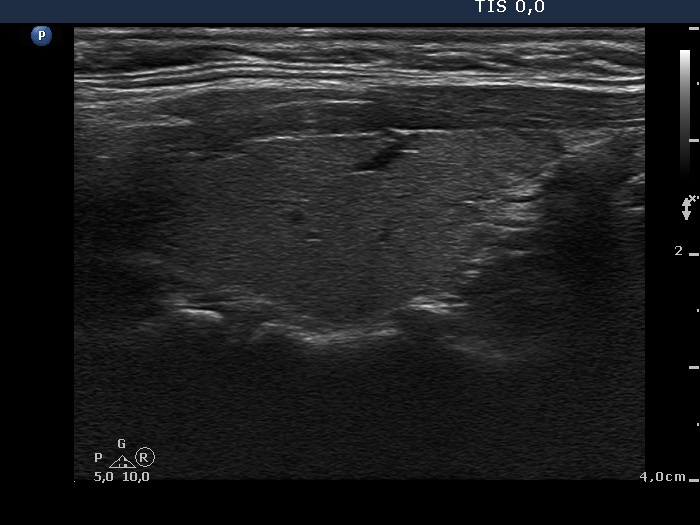

Graves' disease - Case 1080

Follow-up investigation 9 months after first examination (ultrasonographic picture 5)

Right lobe, horizontal view